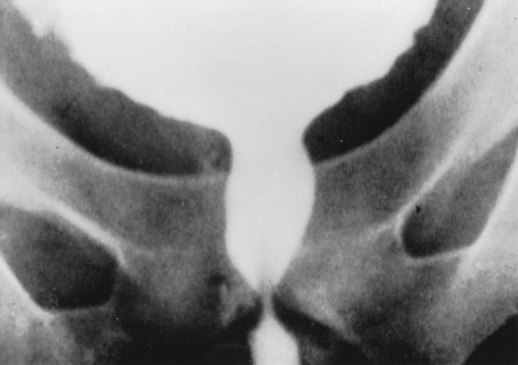

The characteristic pattern that results when a patient has a complete lesion above the sacral spinal cord is detrusor overactivity, smooth sphincter synergia (with lesions below the sympathetic outflow), and striated sphincter dyssynergia (Sullivan and Yalla, 1992; Thomas and O’Flynn, 1994; Chancellor and Blaivas, 1995b). Neurologic examination shows spasticity of skeletal muscle distal to the lesion, hyperreflexic deep tendon reflexes, and abnormal plantar responses. There is impairment of superficial and deep sensation. Figures 65-1 to 65-3 typify the cystourethrographic and urodynamic patterns. The guarding reflex is absent or weak in most patients with a complete suprasacral SCI. In incomplete lesions the reflex is often preserved but variable (Morrison et al, 2005).

The striated sphincter dyssynergia causes a functional obstruction with poor emptying and high detrusor pressure. In an effort to subclassify detrusor sphincter dyssynergia, Karsenty and colleagues (2005) retrospectively evaluated video-urodynamic recordings of patients with complete SCI with untreated neurogenic overactive bladder and detrusor sphincter dyssynergia. They identified two time periods within the tracings, with Delay A being defined as that period between the onset of external urethral sphincter (EUS) pressure increase and the subsequent onset of bladder pressure increase. Delay B was defined as the period between the onset of urethral sphincter pressure increase and the moment at which bladder pressure increase reached a level of 10 cm H2O or greater above the baseline value. The recordings of 20 patients were assessed, with the Delay A timeframe found to be significant in 16 of 20 patients, with a meantime for delay of 2.2 seconds. There was a positive association between this delay and the completeness of the SCI and the presence of continuous DSD on electromyogram. Delay B was positive in all patients with a mean delay time of 7.6 seconds. The authors concluded that EUS contraction starts before the onset of bladder contraction in most patients with coexistent SCI and detrusor sphincter dyssynergia. Occasionally, incomplete bladder emptying may result from what seems to be a poorly sustained or absent detrusor contraction. This seems to occur more commonly in lesions close to the conus medullaris than with more cephalad lesions. This may result from a second occult lesion or may be caused by locally functioning reflex arcs, which result in detrusor inhibition from strong striated pelvic floor muscle contraction, or to a loss of higher center–mediated detrusor facilitation, which normally occurs after the initial increase in pressure during a bladder contraction (Thomas and O’Flynn, 1994). Once reflex voiding is established, it can be initiated or reinforced by the stimulation of certain dermatomes, as by tapping the suprapubic area. The urodynamic and upper tract consequences of the striated sphincter dyssynergia vary with severity (generally worse in complete lesions than in incomplete ones), duration (continuous contraction during detrusor activity is worse than intermittent contraction), and anatomy (male is worse than female) (Linsenmeyer et al, 1998).

After the patient recovers from spinal shock, there is generally a depression of deep tendon reflexes below the level of a complete lesion with varying degrees of flaccid paralysis. Sensation is generally absent below the lesion level. Detrusor areflexia with high or normal compliance is the common initial result, but decreased compliance may develop, a change seen in some neurologic lesions at or distal to the sacral spinal cord that most likely represents a complex response to neurologic decentralization probably involving reorganization and plasticity of neural pathways (Fam and Yalla, 1988; de Groat et al, 1997; Blaivas et al, 1998b). There is surprisingly little consensus on the evolution of the appearance or function of the bladder neck or smooth sphincter area after sacral spinal cord damage. The classic outlet findings are described as a competent but nonrelaxing smooth sphincter and a striated sphincter that retains some fixed tone but is not under voluntary control. Closure pressures are decreased in both areas (Sullivan and Yalla, 1992; Thomas and O’Flynn, 1994). However, the late appearance of the bladder neck may be “open” (Kaplan et al, 1991). Attempted voiding by straining or Credé’s maneuver results in “obstruction” at the bladder neck (if closed) or at the distal sphincter area by fixed sphincter tone (Fam and Yalla, 1988; Thomas and O’Flynn, 1994). Figure 65–4 illustrates the typical cystourographic and urodynamic pictures of the late phases of such a complete lesion.